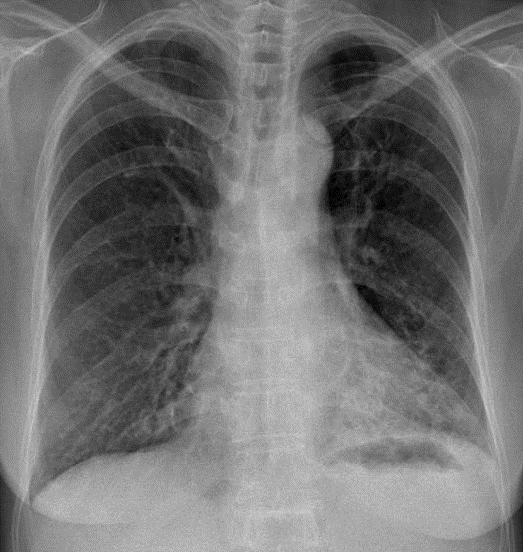

Hãy phân tích tình huống Nữ 68 tuổi

1-Tổn thương mô kẻ rải rác thùy dưới hai phổi (T)>(P) => Viêm phổi + dãn phế quản dạng túi